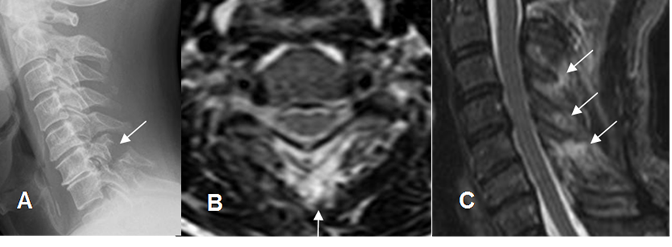

B: RM axial en T2 y C: RM sagital en STIR. Cambios inflamatorios en los tejidos blandos e hiperintensidad, por lesión de los ligamentos interespinosos.

Fig 205 A. Fractura en lágrima.

A y B: Rx lateral. Fracturas complejas con anterolistesis G IV. Se encuentran fragmentos óseos anteriores, alineados con el cuerpo superior. (Flechas).

Fig 206 A. Luxación de facetas.

A: TAC reconstrucción sagital. Anterolistesis post-traumática.

B: TAC axial y C: TAC reconstrucción sagital. Luxación de las articulaciones interapofisiarias, con desplazamiento anterior de las facetas superiores. (Flecha delgada). Facetas normales en el segmento inferior. (Flecha gruesa).

Fig 206 B. Luxación de facetas.

A: RM sagital en T2. Igual paciente anterior. Anterolistesis post-traumática, con sección medular. (Flecha delgada).

Presencia de colección prevertebral. (Flecha gruesa).

B: RM sagital en T2. Luxación de las articulaciones interapofisiarias, con desplazamiento anterior de las facetas superiores. Facetas normales en el segmento inferior. (Flecha gruesa).